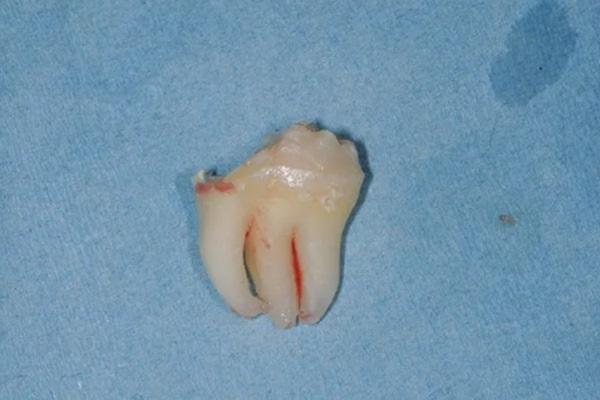

После того, как слизисто-надкостничный лоскут был приподнят, обнажился пораженный третий моляр и окружающая кость. Третий моляр был удален в ходе выполнения вестибулярной остэктомии с помощью углового наконечника и круглого твердосплавного бора. После вывиха третьего моляра мезиальная часть зубной коронки была сначала разрезана с помощью углового наконечника и твердосплавного бора и удалена. Остаточная часть третьего моляра была удалена с помощью элеватора (Фото 4).

Фото 4: Вестибулярный вид удаленного аномального третьего моляра.